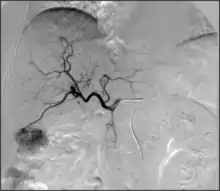

- Kidney cancer: kidney tumors such as renal cell carcinoma can be treated with image-guided ablation (RFA, MWA, cryotherapy) with similar results to partial nephrectomy. Generally, surgery via an either partial or total nephrectomy (removal of kidney) is most often curative but for patients with a smaller lesion or who are not ideal surgical candidates, radiofrequency or cryoablation ablation can be a curative option.[70] Advantages of cryoablation include the ability to visualize the ice ball as well as use more than one probe simultaneously to create the desired ice ball shape. Benign kidney tumors such as angiomyolipomas can be treated with transarterial embolization to shrink the tumor size and reduce the risk of rupture/bleeding. Other embolizations are also performed for symptom relief or prior to surgery to reduce bleeding.[71]